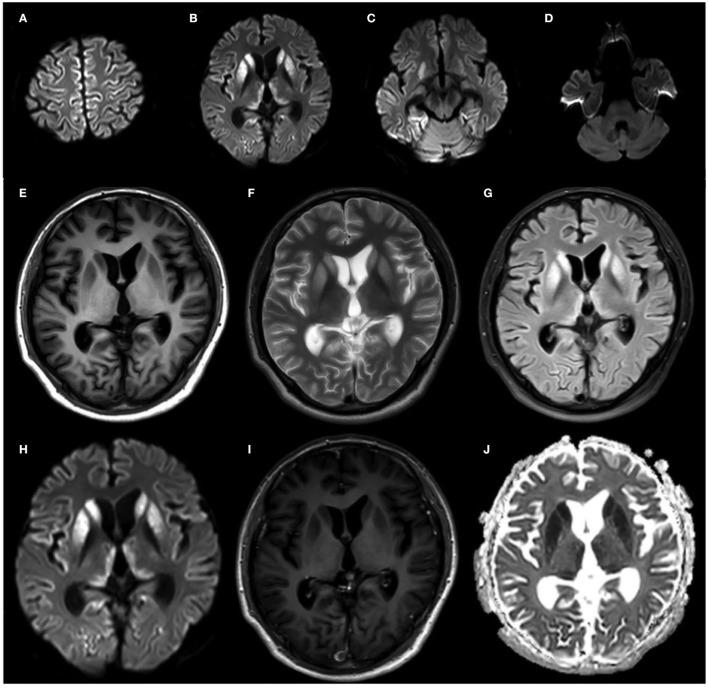

遗传性克雅氏病(gCJD)以朊蛋白(PrP)基因突变()为特征,约占人类朊病毒病总数的10%-15%。在此,我们报告一个汉族家庭中该基因的罕见突变。一名36岁男性起初出现焦虑和抑郁,随后发展为进行性痴呆、齿轮样强直伴震颤,最初两年被诊断为额颞叶痴呆。疾病进展相对缓慢,4年后患者发展为运动不能性缄默症。为明确该疾病,在进行系谱研究、神经心理学检查、神经影像学研究、实时震颤诱导转化(RT-QuIC)检查等之后,我们最终通过DNA测序在患者的PrP中鉴定出一种罕见的G114V突变并伴有一个八肽重复序列缺失(1-ORPD)。此外,随后在患者无症状的母亲身上也发现了相同的突变和缺失。他的外祖母在60多岁时发病较晚。鉴于此前人类朊病毒病中从未报道过1-OPRD,我们首次报道该家庭中同时出现G114V突变和1-OPRD,这将增进我们对gCJD病因机制的理解。